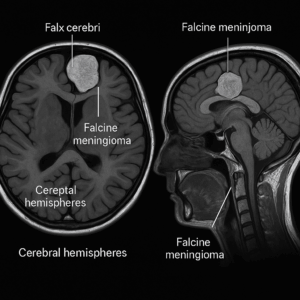

Falcine meningiomas arise from the falx cerebri, the midline dural fold that separates the two cerebral hemispheres. As these deep, midline tumors enlarge, they press on the inner surfaces of the hemispheres and may trigger brain swelling (edema). Consequently, patients can develop neurologic symptoms and functional decline. These tumors most often occur along the falx in the frontal, parietal, or occipital regions.

A falcine meningioma arises from the falx cerebri, the membrane that separates the brain’s hemispheres. As it enlarges, it presses on nearby cortex and midline veins.